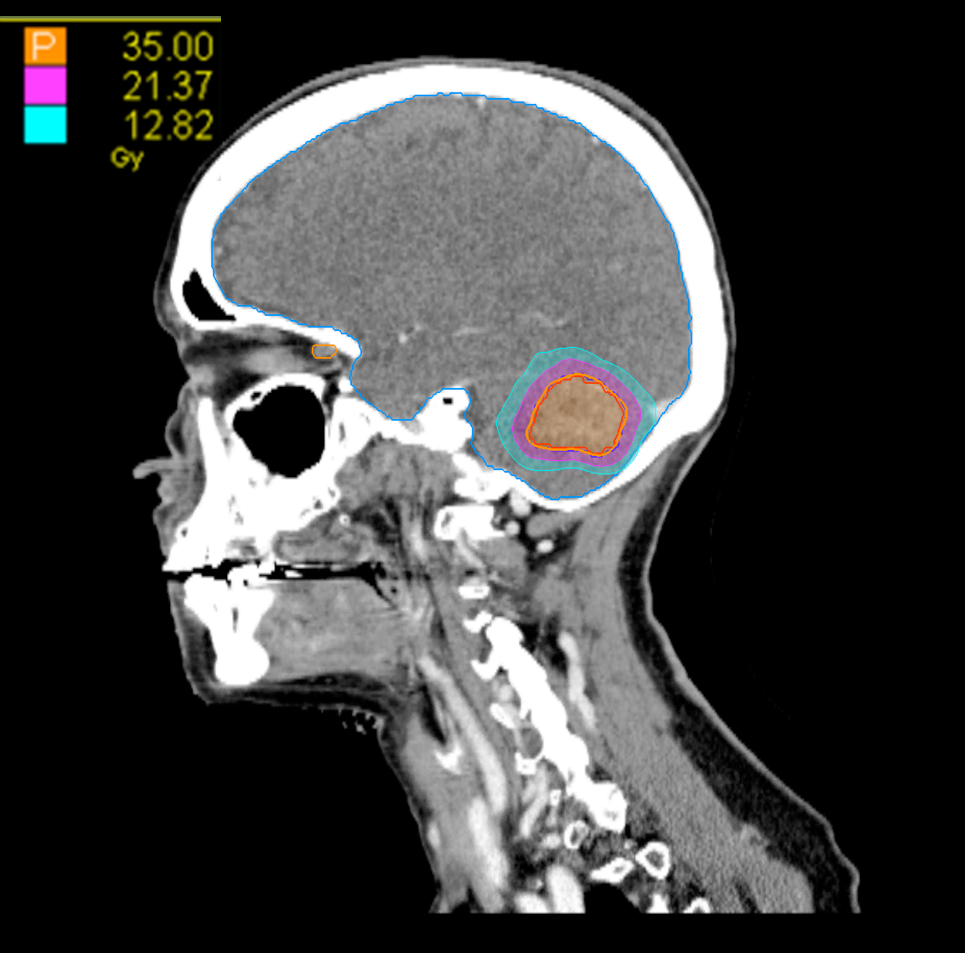

Treatment Plan Images

Dose Distributions

- Prescription to the 82% isodose line

- Max. dose 42.7 Gy

35 Gy in 5 fractions

Gradient Index (GI)

GI = 3.07